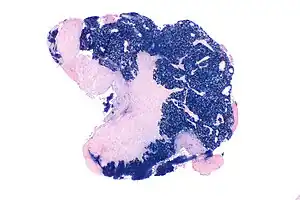

![]() | |

| Micrograph showing a nasopharyngeal carcinoma positive for Epstein-Barr virus-encoded small RNAs (EBER). | |